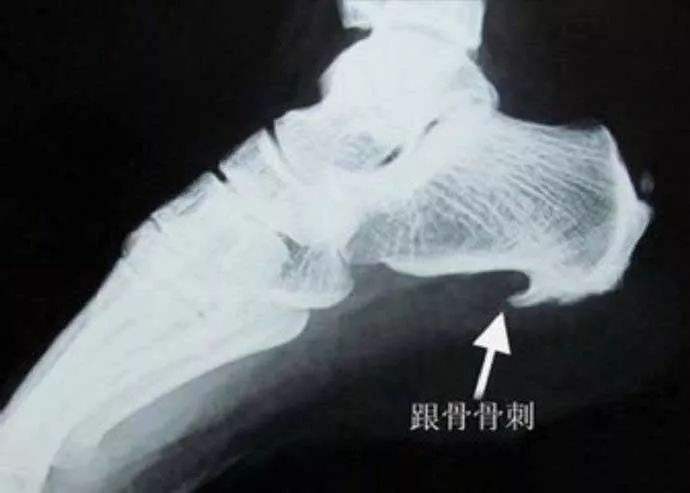

足跟痛也叫“跟痛症”,科普一下什么是跟痛症,跟痛症是指一侧或两侧足跟部的疼痛为主要临床表现的多种疾病的总称,很多病人下床时不敢足跟直接着地,初着地时疼痛难忍,行走一会儿反而减轻,局部不红不肿,还有一些病人自觉足跟部疼痛,但是在局部却按不到明确的压痛点,医院行常规X片检查,往往会在足跟骨前方发现一个类似于鸟嘴的骨刺,那这个骨刺真的就是足跟痛的唯一原因吗?我们试着来分析下!

跟骨骨刺几乎无一例外的尖端向前!

说了这么多足跟痛,重回主题,再谈跟骨骨刺,在足跟痛的患者中,很多人都有足跟骨刺的存在,那骨刺到底会不会引起足跟痛呢?我的回答是,一部分人的跟骨刺,是可以引起足跟痛的,但仅仅是一部分而已!

曾经有人做过调查,大约30%的人从三十岁开始就会出现跟骨骨刺,随着年龄的增长,跟骨骨刺的检出率逐年提高,到七十岁时,跟骨骨刺的检出率就几乎百分之百了,但事实上,七十岁的人并不是百分百出现足跟痛,真正跟骨骨刺引起的疼痛只是很少的一部分人群而已。从X片上,大家可以观察到,几乎所有的跟骨骨刺都是尖端向前的,为什么会出现这种情况呢?这就要谈到足跟骨刺的产生机理了!

针刀创始人朱汉章教授是最早否认骨质增生退变学说的专家之一了,他把骨质增生的原因归责于三种力,压应力、涨应力和拉应力,而跟骨骨刺就是“拉出来的”,前面说过,足底肌腱就像一根弹簧,维持着足弓的稳定,而足跟骨前侧是拉应力最集中的地方,随着足底韧带的反复牵拉,难免会在跟骨附着点处出现韧带损伤,人体为了修复这种损伤,就会调集大量的钙离子沉积在足底韧带跟骨附着点处,久而久之,就形成了尖端向前的跟骨骨刺,所以说,跟骨骨刺只不过是人体的一种自我修复、加强防御罢了,极少数人群修复过程中,会造成对穿行其中的末梢神经的卡压,或伴有不同程度的无菌性炎症,而出现足跟痛,这种足跟痛是最好解决的,我们只需要一枚小针刀,在骨刺尖端切断几根紧张的韧带纤维,卸掉过大的拉应力,足跟疼痛就会立马消失!值得一提的是,很多跖筋膜炎、跟骨脂肪垫炎、跟骨骨刺的引起的疼痛都是并存的,如果按疼痛部位详加区分,跖筋膜炎多位于跟骨前内侧,脂肪垫炎多位于跟骨正中,跟骨骨刺多位于跟骨正前方位置!在笔者写这篇文章的时候,正好有一对老夫妻都是因为足跟痛来诊,笔者就几种临床常见证型做了简单分析,同时录制视频一篇,感兴趣的亲们可以关注下!